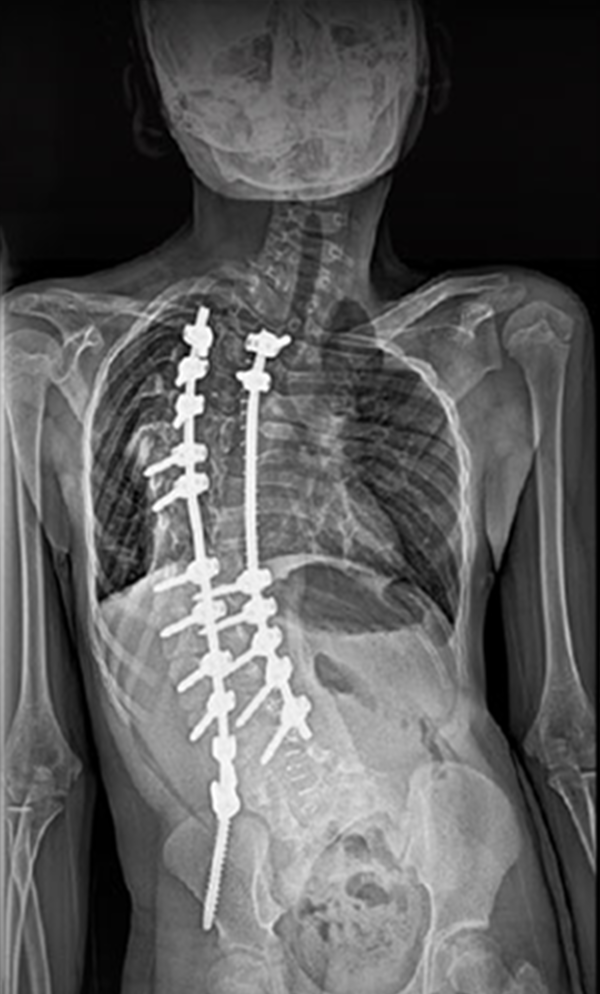

BEYOND RECOVERY : REAL STORIES

Gallery : Before - After